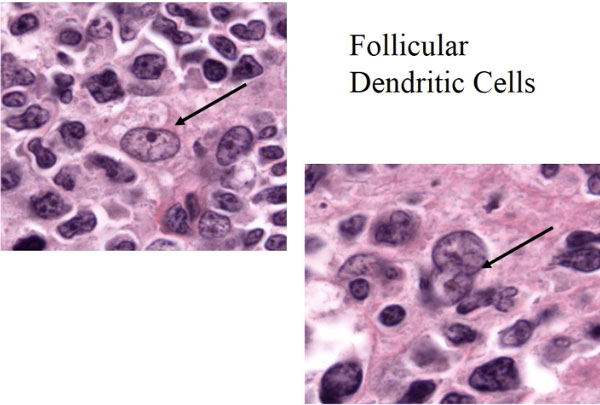

- difficult to distinguish from lymphoma w/ advanced differentiation of plasma cells

-- immune-/plasmablastic cell lymphomas, esp. marginal zone lymphoma of MALT